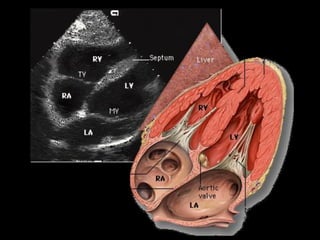

APICAL